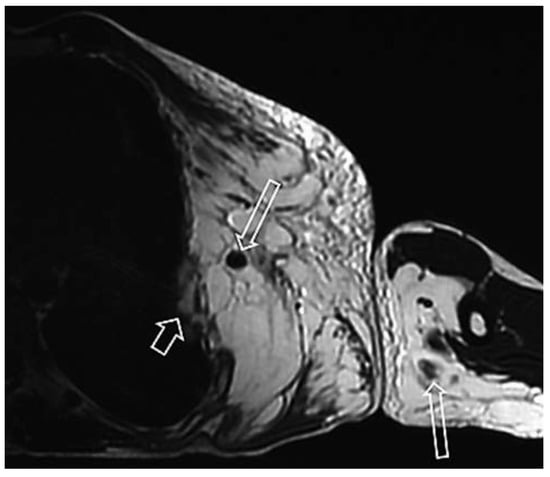

Case report A 22-year-old male experienced a presyncopal spell while studying for a university examination [...]